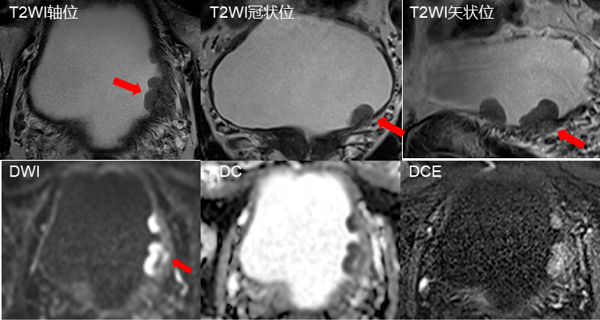

病例展示

图片1

符合Ⅵ-RADS4分